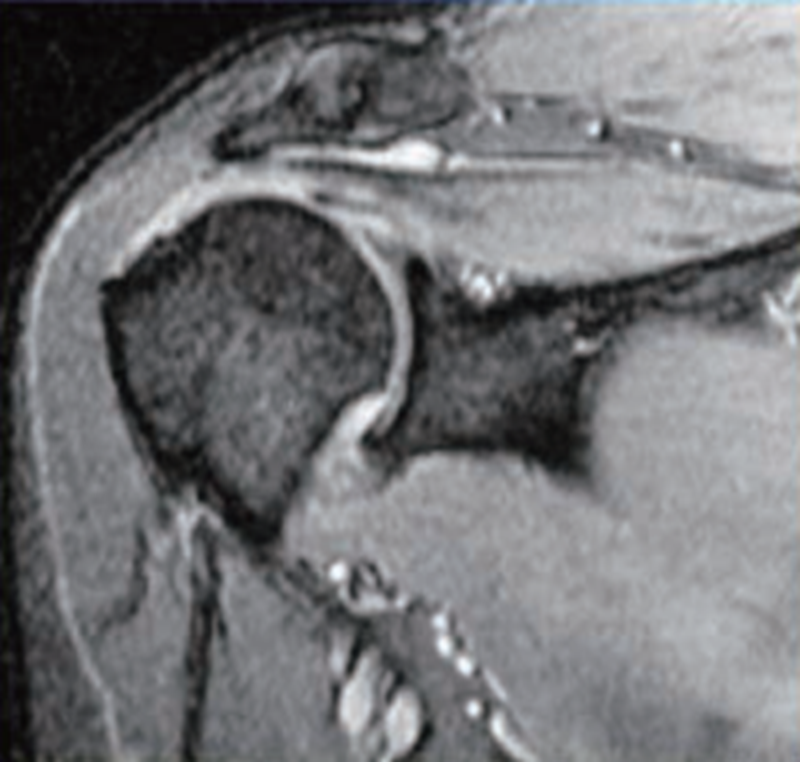

MRI检查是目前在诊断肩袖疾病中最常用的检查方法,对全层肩袖损伤的敏感性和特异性分别高达96%和98%,因此成为目前判断肩袖损伤最为有效的辅助检查方法。

斜冠状位可以很好地判断冈上肌损伤的情况,T1像可以显示肌腱完整性的丧失,但T2像更为清晰,尤其是T2压脂像,去除了脂肪组织的干扰,可以清晰显示冈上肌撕裂后在局部造成的水样高亮信号影(图8)。在斜冠状位上还可以观察肌腱向内侧回缩的程度。

图8 MRI示冈上肌全层撕裂